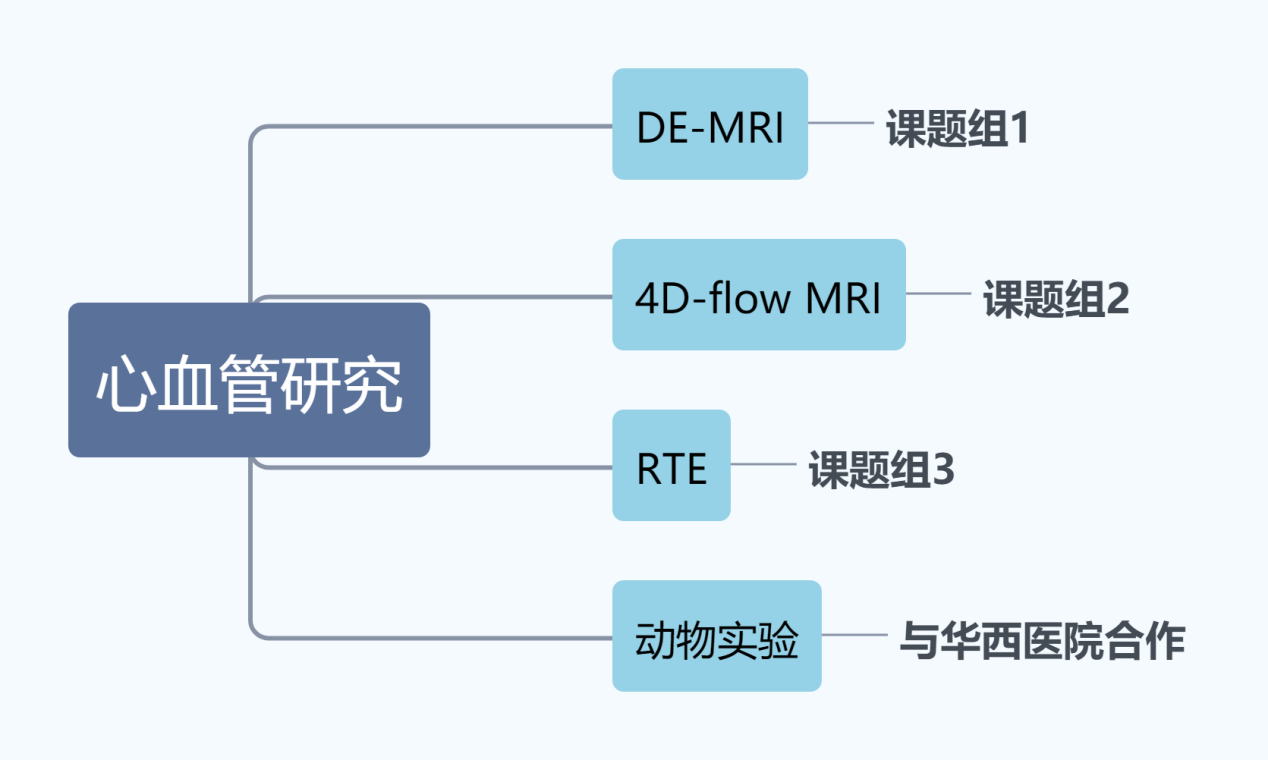

Kelvin Wong团队心血管研究课题组分工

图4 团队课题组分工

团队主要进行心血管研究,团队下设三个课题组(如图4所示),分别进行DE-MRI技术研究、4D Flow MRI技术研究和RTE技术研究,而动物实验主要通过与华西医院进行合作。每个团队都在国际期刊上发表了顶级杂志的文章,描述了基于4D flow MRI成像的左心房流体力学变化介导的心房结构重构在心房纤颤的发生与发展作用及机制以及基于4D 磁共振和超声弹性成像技术的心房纤维化在心房颤动中的作用及机制。